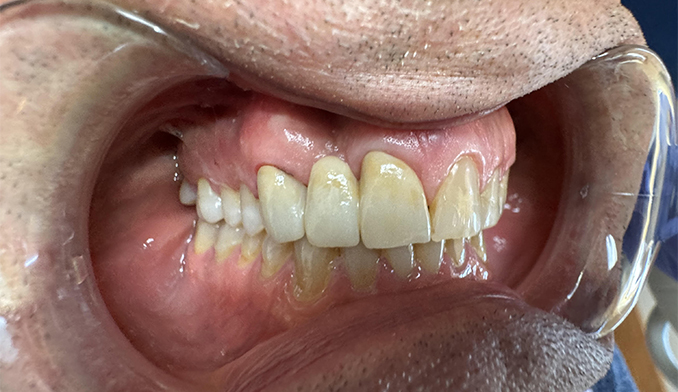

Gumline Bonding for Esthetics and Protection

The patient requested bonding along the gumline to improve appearance and protect exposed areas. We placed tooth-colored fillings to restore a smooth, natural look and enhance long-term oral health.